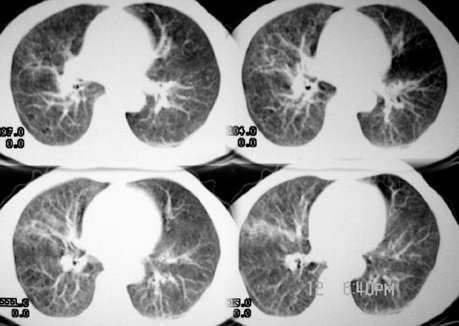

郁闷!病灶和主动脉弓是宽基底相连,但主动脉弓壁是清晰可见;肺窗示病灶边缘见不规则毛刺样改变;肝左叶见巨大囊性病灶。我考虑胸部病灶是纵隔型肺癌,肝内病灶不好说是啥。

3、两肺间质纤维化;

支气管内侧壁和左上肺静脉分界不清(尖后段支气管未见明显狭窄)双肺血管纹理明显增多

以右侧明显并可见胸膜下线 不规则线状影和中叶的斑片状影;左膈明显升高。

影象诊断:考虑纵隔型肺癌伴纵隔淋巴结转移.肺内炎变待除外.肺内转移建议hrct

病灶和主动脉弓是宽基底相连,但与主动脉弓壁之间的脂肪间隙清晰可见;肺窗示病灶边缘有不规则毛刺样;左肺叶段肺气肿;左侧横膈升高。右肺中叶炎变;结合病史考虑纵隔型肺癌可能性大。其他的难说!

左上肺纵隔旁可见一形态略不规整的软组织肿块,与主动脉弓壁之间的脂肪间隙清晰,肺窗示病灶边缘有不规则毛刺样改变,右肺中叶炎症。综合病史考虑纵隔型肺癌。